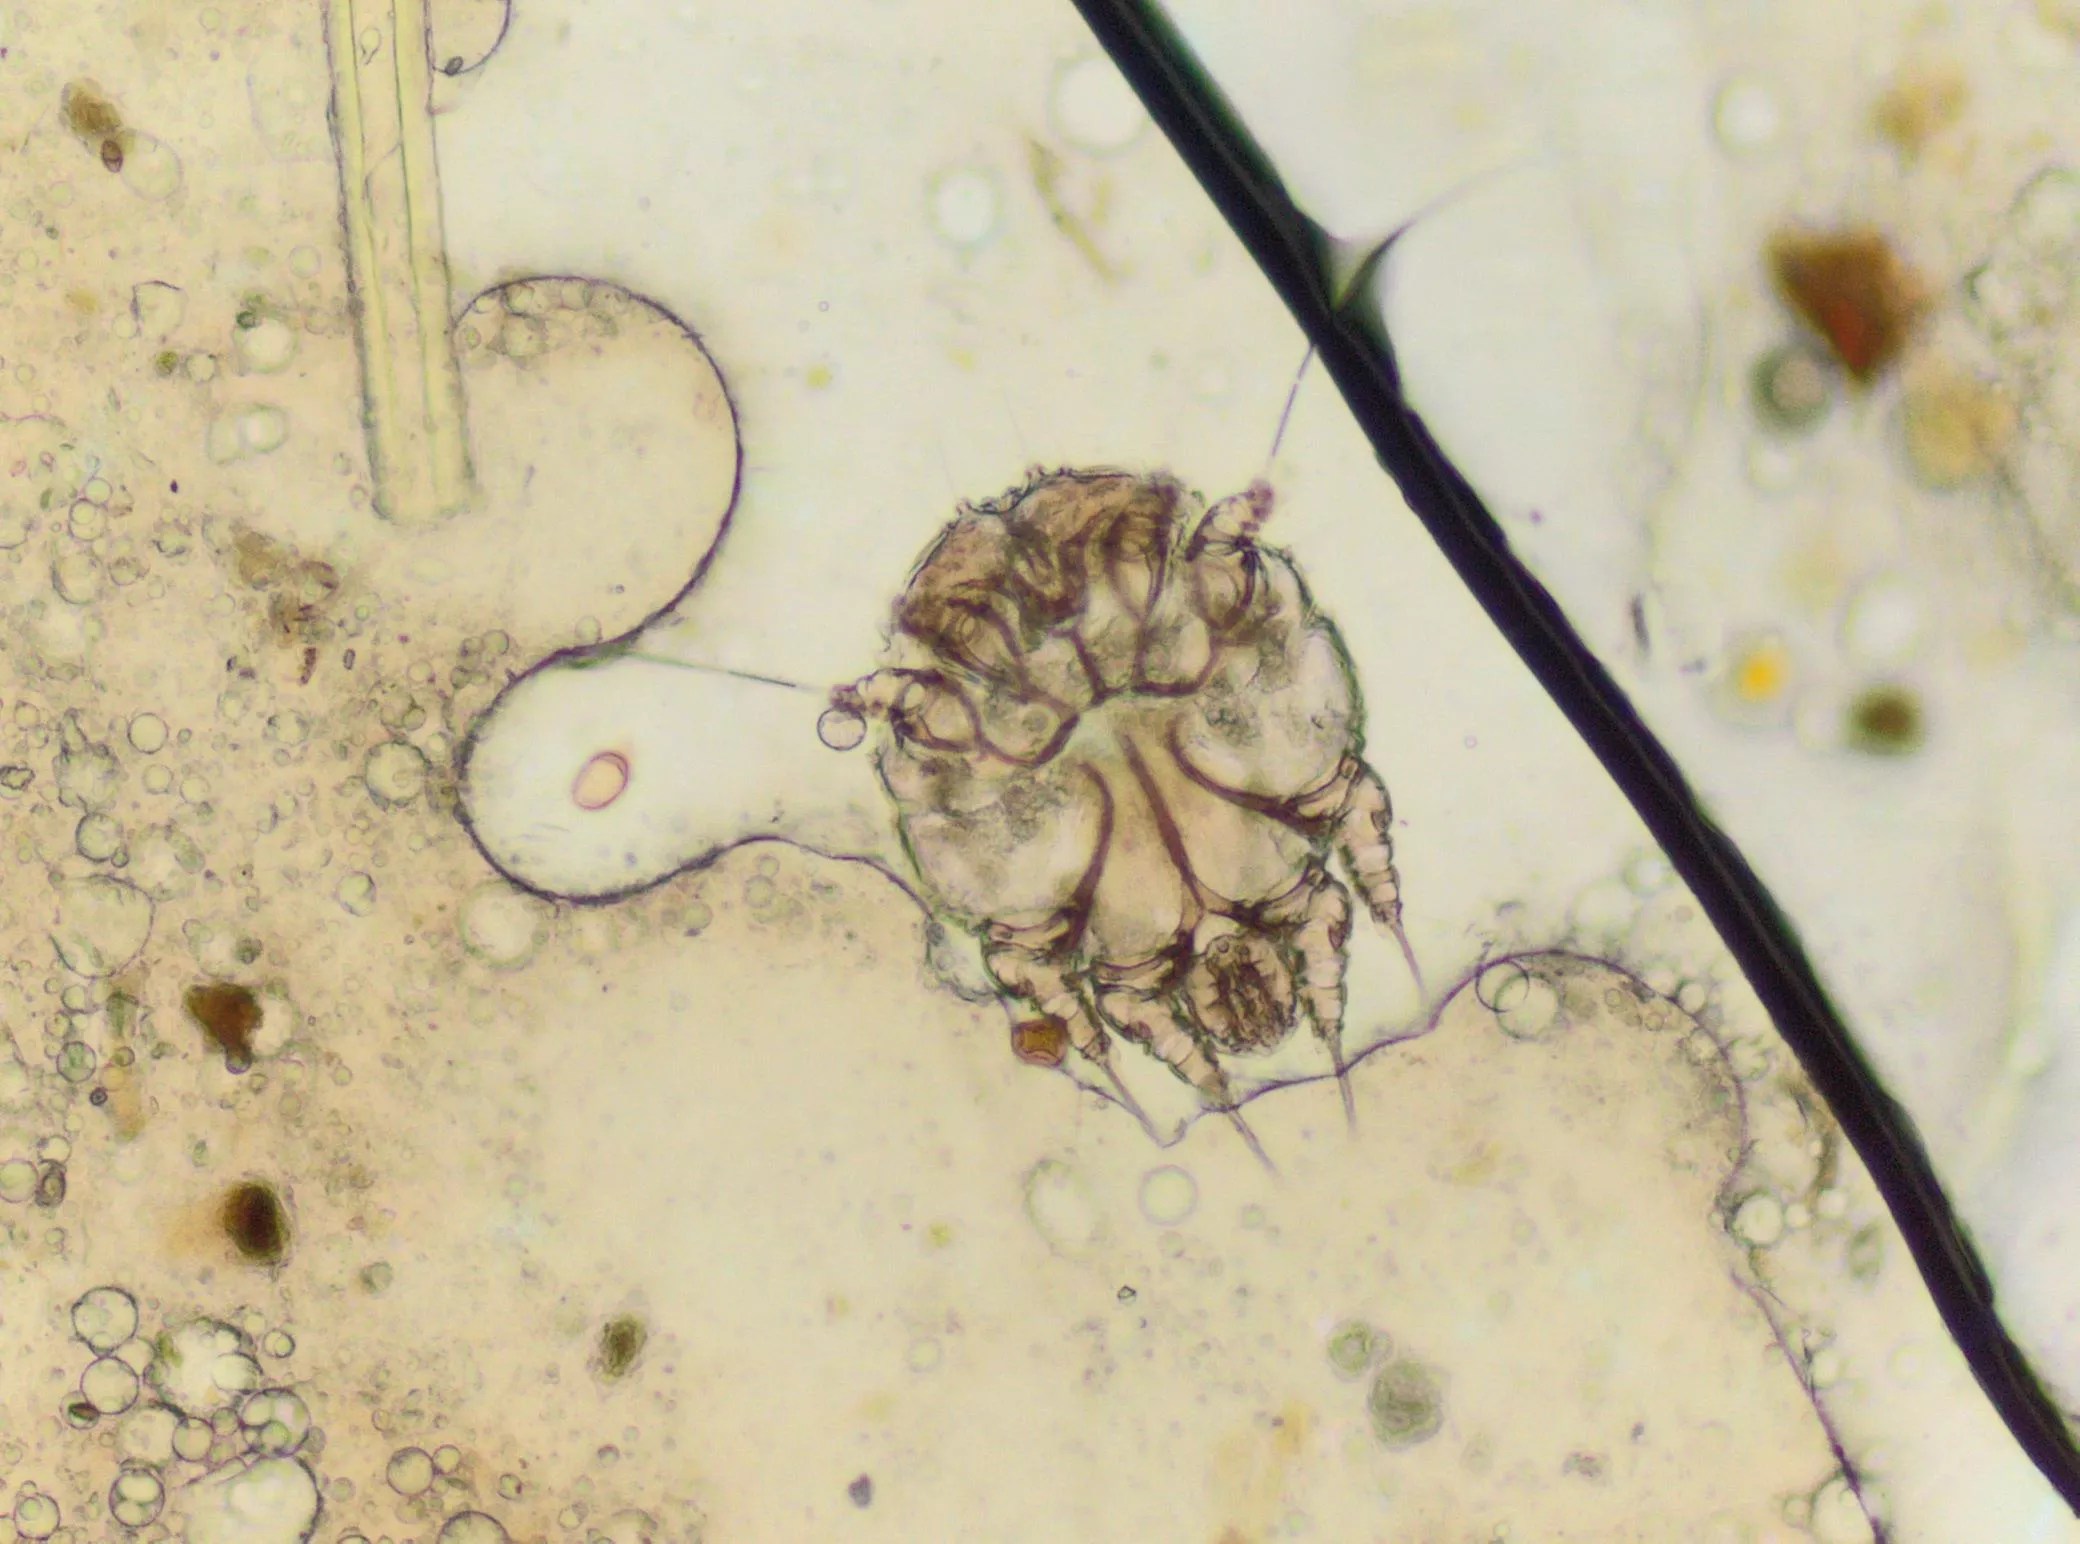

A microscopic view of the mite that causes scabies.

Scabies occurs when a human itch mite burrows into the upper layer of the skin, where it lives and lays its eggs. When a person is infected with scabies for the first time, they can be contagious, even while not displaying symptoms for weeks.